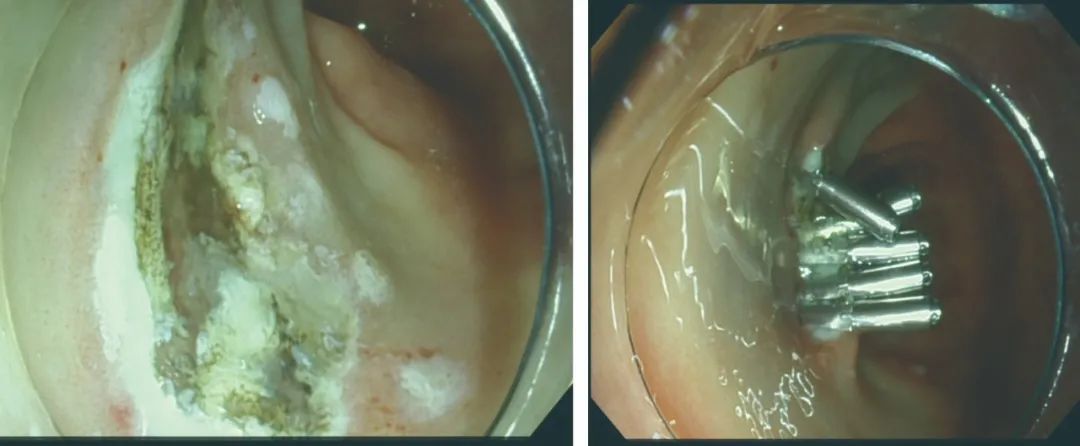

▲病灶剥离,处理创面